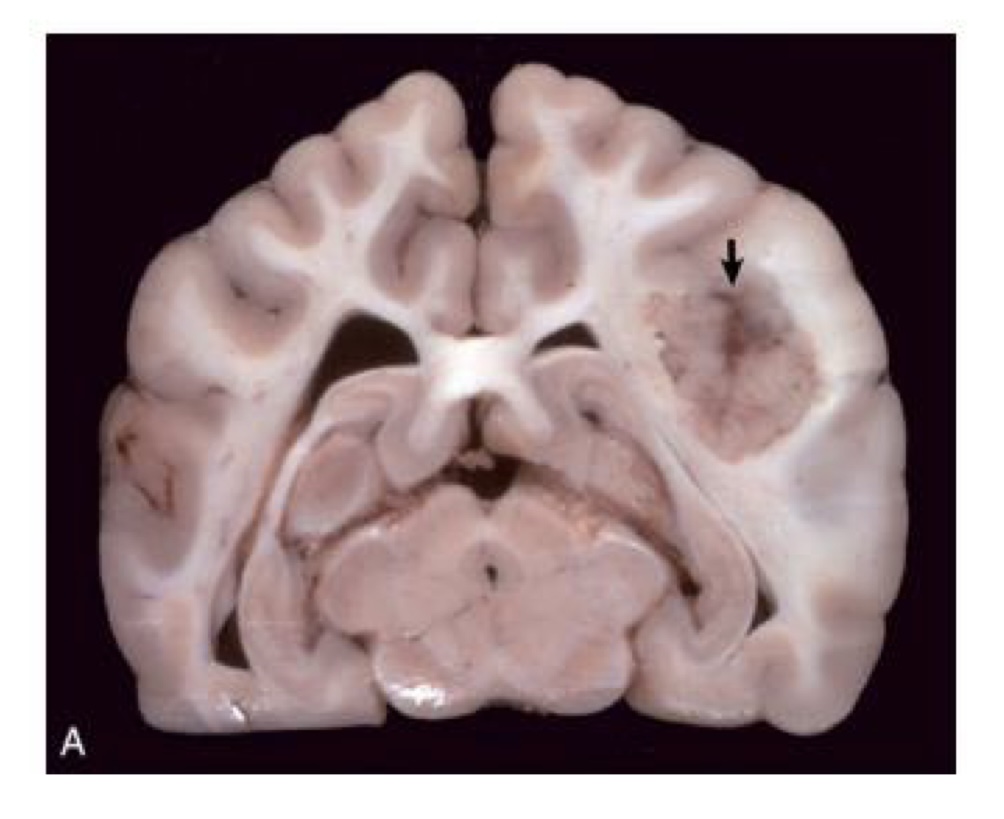

what is this?

astrocytoma

right hemisphere contains a poorly demarcated, nonencapsulated, expansile mass

lesion has displaced the midline to the left and compressed the right lateral ventricle